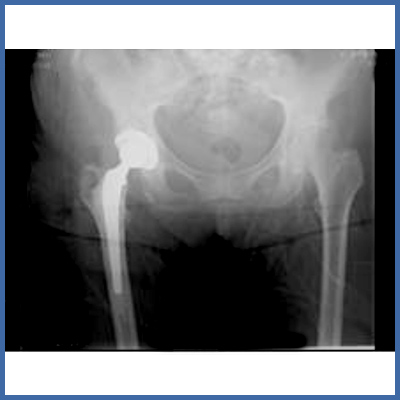

Dank neuen Implantaten, Operationsinstrumenten und intraoperativen Lagerungsmöglichkeiten stehen uns mittlerweile Wege offen, auch bei fortgeschrittenen Arthrosen mit geringem Aufwand das Gelenk ersetzen zu können.

Minimalinvasiv heisst nicht eine möglichst kleine Operationsnarbe; man versteht darunter, dass nur wenige anatomische Strukturen weggehalten oder nur teilweise abgelöst werden müssen. Nur so ist eine sofortige Belastung möglich resp. erlaubt.

Diese Operationstechniken sind mittlerweile auch bei Revisions-Operationen möglich, z.B. bei einer gelockerten Prothese, oder bei einem Materialbruch.

Das Röntgenbild nach Implantation der Hüftprothese.